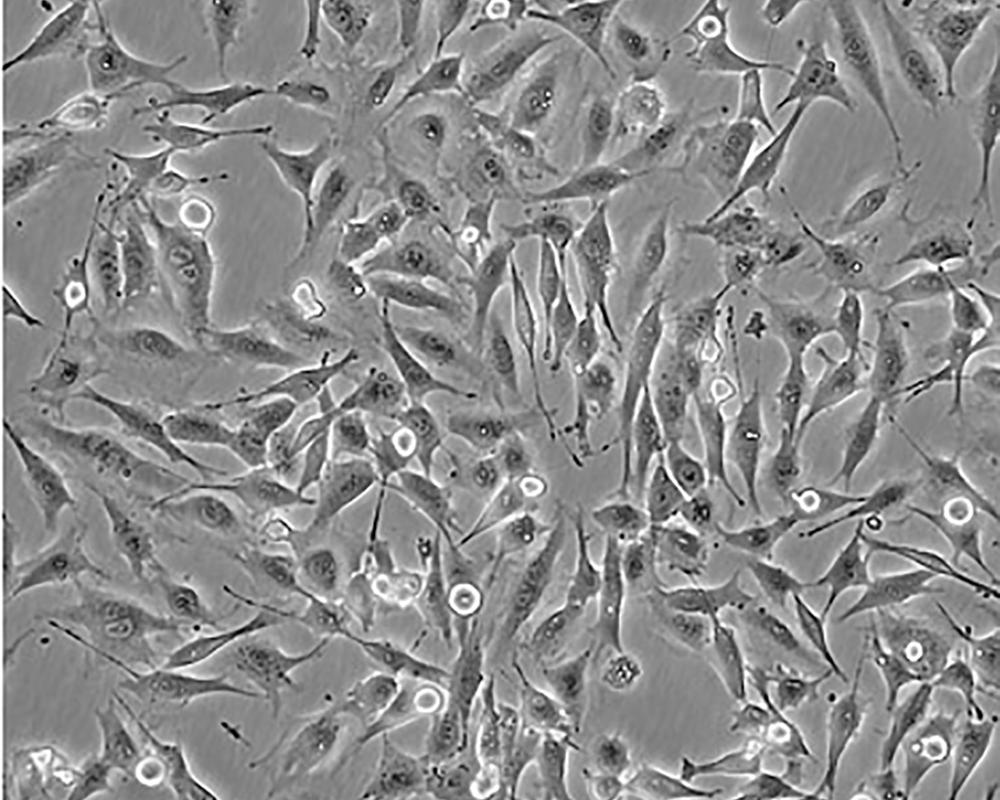

形態特征 spindle shaped

細胞描述 MDA-MB-435S是一種紡錘形的細胞,1976年由其親本(435)中篩選得到。435是從31歲的轉移性乳腺導管腺癌女性患者胸水中分離得到。當用熒光染料對微管蛋白進行染色時親本細胞顯現散布特征(II型)。最近通過cDNA陣列研究表明,親本(MDA-MB-435)可歸入黑素瘤起源。